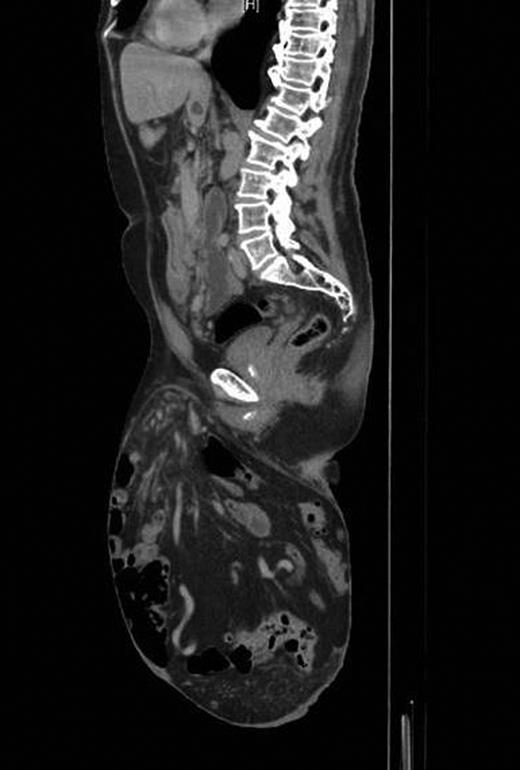

On follow-up after 8 weeks, the patient was in a very good general condition with intact hernia repair and laparotomy wound. He was found to have a moderate scrotal swelling (Fig. 3) which proved by CT scan to be a postoperative seroma (Fig. 4) which was managed conservatively.

Postoperative CT scan showing intact repair and clear fluid in the scrotum.